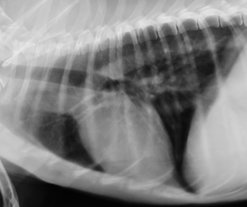

左下が胸部レントゲン写真で、寄生虫性肺炎気管支炎を示しております。写真のワンちゃんは生後1年弱、糞線虫が治療されていませんでした。右下の写真は正常レントゲン写真です。

寄生虫性肺炎.jpg 正常胸部写真.jpg